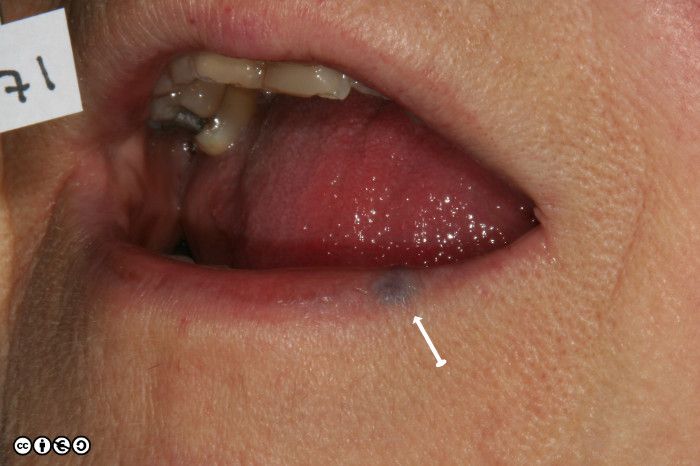

One variety referred to as a venous lake, is commonly seen on the lips, is easily compressible and is often confused with melanotic macules of the lips which are not compressible (discussed in the previous chapter).